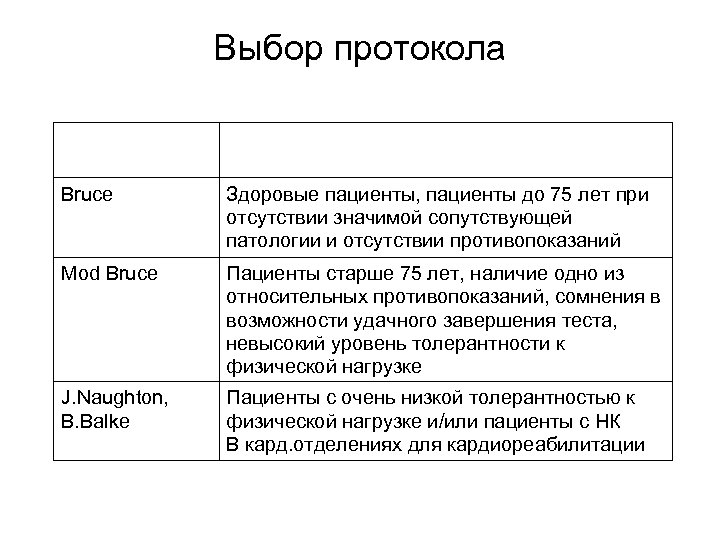

Выбор протокола Протокол Категория пациентов Bruce Здоровые пациенты, пациенты до 75 лет при отсутствии значимой сопутствующей патологии и отсутствии противопоказаний Mod Bruce Пациенты старше 75 лет, наличие одно из относительных противопоказаний, сомнения в возможности удачного завершения теста, невысокий уровень толерантности к физической нагрузке J. Naughton, B. Balke Пациенты с очень низкой толерантностью к физической нагрузке и/или пациенты с НК В кард. отделениях для кардиореабилитации

Выбор протокола Протокол Категория пациентов Bruce Здоровые пациенты, пациенты до 75 лет при отсутствии значимой сопутствующей патологии и отсутствии противопоказаний Mod Bruce Пациенты старше 75 лет, наличие одно из относительных противопоказаний, сомнения в возможности удачного завершения теста, невысокий уровень толерантности к физической нагрузке J. Naughton, B. Balke Пациенты с очень низкой толерантностью к физической нагрузке и/или пациенты с НК В кард. отделениях для кардиореабилитации